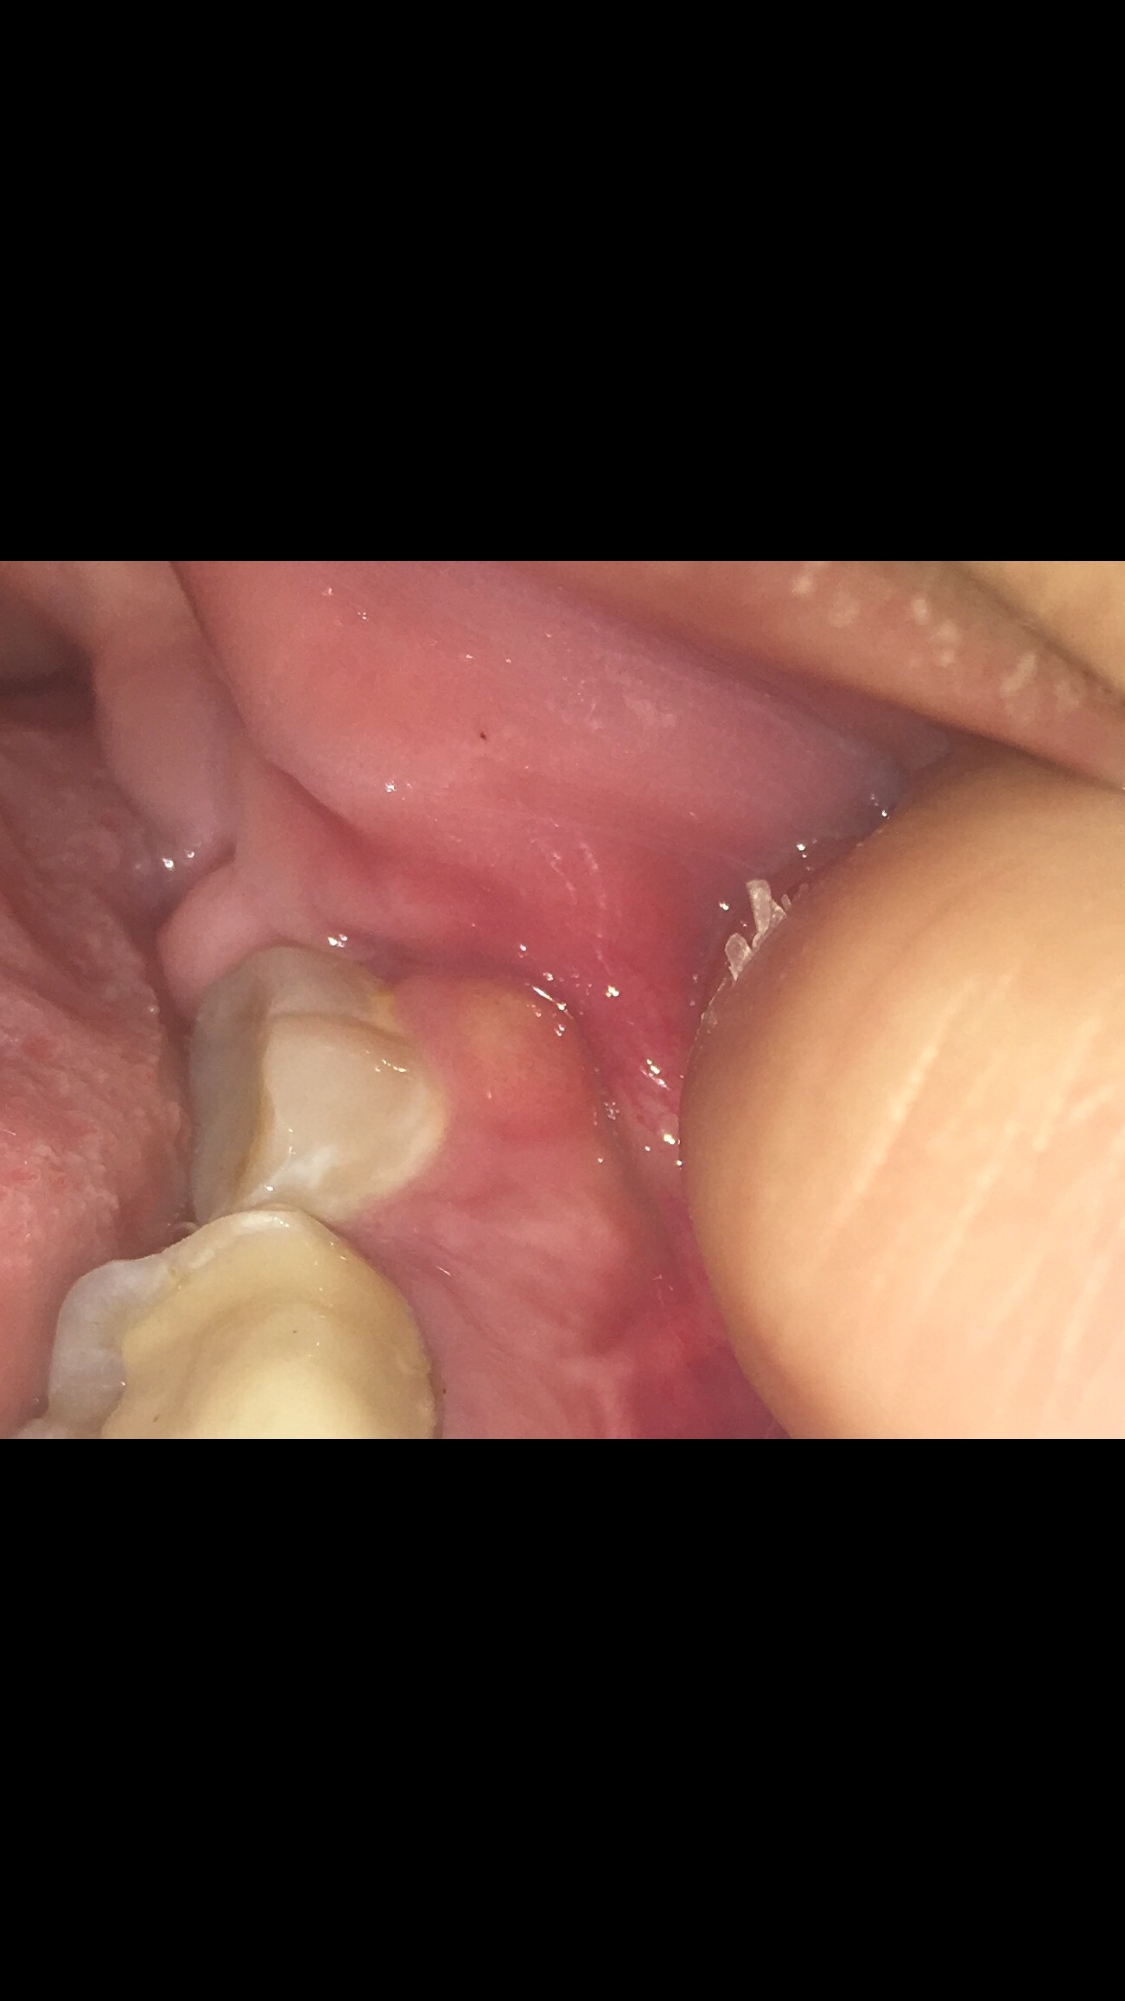

Beule am zahnfleisch ohne schmerzen. Die braucht sie dann auch. In diesen Fällen sollte man am besten zwei bis drei Tage abwarten und schauen ob sich die Situation bessert. Das sieht nach einer stark entzündeten Zahnfleischtasche aus.

Am Zahn und Zahnfleisch können viele Probleme entstehen. Die beuele ist vermutlich ein sich ausbildender abszeß der von alleine nicht besser wird auch die schmerzen werden nicht besser. Der wird die Stelle behandeln und ihr wahrscheinlich Antibiotika verschreiben.

Weitere Auslöser können sein. Eine Eiterbeuleentsteht durch die Entzündung im Knochen und am Zahn. Probleme am Zahn wie Zyste Fistel Eiter Schwellung.

Zahnentzündung apikal bedeutet dass sich die Entzündung an der Wurzelspitze befindet. Das Anschwellen vom Zahnfleisch und evt. Wenn die Wurzel am Zahn entzündet ist macht sich dies meist bemerkbar durch die Schmerzen und ein leichtes anschwellen vom Zahnfleisch.

Dehnt sie sich bis zum Kieferknochen aus heißt. Deshalb empfindet der Betroffene keine Schmerzen obwohl sich die Entzündung mit großer Wahrscheinlichkeit schon tief in den Kiefer hinein vorgearbeitet hat. Ein traumatischer Zahnunfall oder eine Verletzung.

Entweder wurde das Zahnfleisch durch mechanische Reize verletzt oder eine Infektion mit Viren Bakterien oder Pilzen ist schuld an der Entzündung. Die Beule ist unnachgiebig aber sie ist ja noch ein Kind. Diese Bakterien können einen Abszess verursachen selbst wenn die Zähne gesund und frei von Löchern sind.

Mit der richtigen Betäubung ist die Behandlung vom Zahn ohne Schmerzen. Eine Schwellung des Zahnfleisches ist ein Anzeichen für eine Entzündung.

Es entsteht ein sogenannter Abszess. Sie sollten jedoch sofort Ihren Arzt anrufen wenn Sie zusätzlich zu einer Beule eines der folgenden Symptome bemerken. Werde auf jeden Fall zum Zahnarzt müssen habe aber eine riesen Angst das sich nun eine Wurzelentzündung oder sogar noch schlimmeres dahinter verbergen könnte. Damit muss sie DRINGEND zum Zahnarzt. Das kann an einer leichten Entzündung oder einer Wucherung liegen. Zudem ist das frühe Stadium einer Infektion des Zahnfleisches meist schmerzlos. Ist ein Zahn oder ein Zahnnerv entzündet schmerzt nicht nur der Zahn selbst. Die braucht sie dann auch. Fragt am besten den Ärztlichen Bereitschaftsdienst Tel.

Sie sollten jedoch sofort Ihren Arzt anrufen wenn Sie zusätzlich zu einer Beule eines der folgenden Symptome bemerken. Mit großer wahrscheinlichkeit ist der zahn abgestorben kann auch symptomolos passieren. Deshalb empfindet der Betroffene keine Schmerzen obwohl sich die Entzündung mit großer Wahrscheinlichkeit schon tief in den Kiefer hinein vorgearbeitet hat. Fragt am besten den Ärztlichen Bereitschaftsdienst Tel. 116 117 wer heute Zahnärztliche Bereitschaft macht. Damit muss sie DRINGEND zum Zahnarzt. Weitere Auslöser können sein.